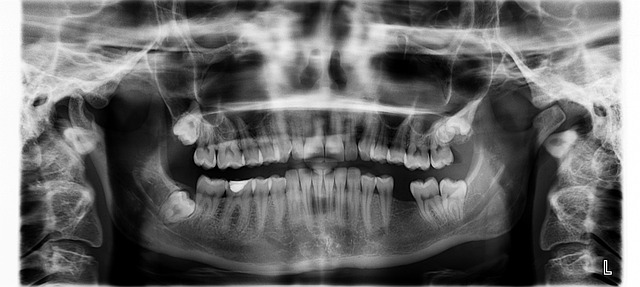

- 뼈이식, 상악동 거상술 등 추가 수술 여부